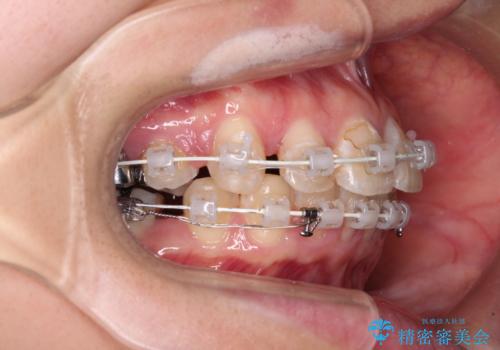

目立たないワイヤー装置にて抜歯矯正を行うこととしました。

下顎は過剰歯が埋伏しており、それが原因となってスペースが閉じなかったため、途中で抜歯して速やかに仕上げました。